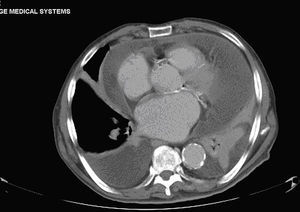

The chest X-ray showed cardiomegaly on admission, with no other findings. A few days later the patient presented an associated bilateral pleural effusion, predominantly on the left side (Fig. 1). A CT of the chest and abdomen reported a pericardial and pleural effusion, moderate in amount and of free morphology, causing a passive collapse of the basal segments of both lower lobes with the rest showing no abnormalities.2